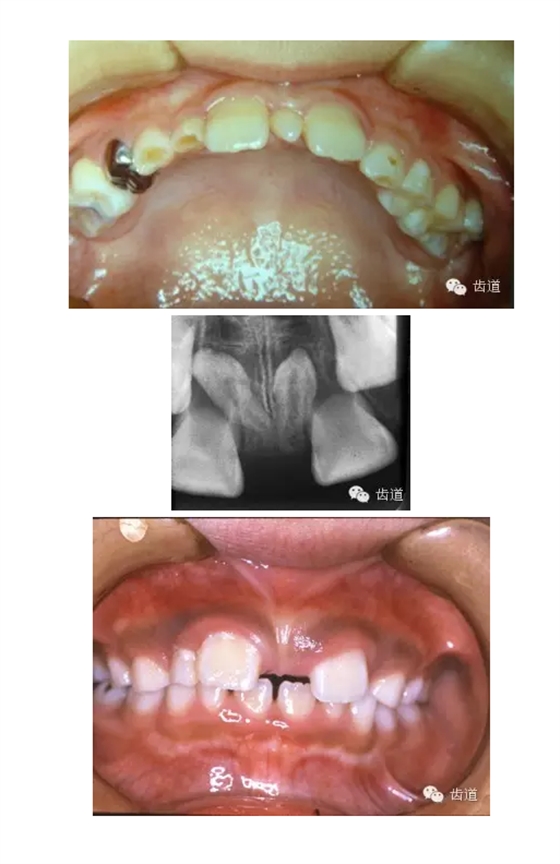

乳牙滯留是指繼承恒牙已萌出,未能按時(shí)脫落的乳牙,或恒牙未萌出,保留在恒牙列中的乳牙及時(shí)拔除

超過正常牙數(shù)以外的牙齒

好發(fā)部位:上頜中切牙之間、牙弓末端第三磨牙之后

多呈圓錐形、圓柱形

影響恒牙的發(fā)育和萌出

應(yīng)及時(shí)拔除

1.奶瓶齲:主要發(fā)生于上頜乳切牙的唇面,較快發(fā)展成廣泛性齲

2.環(huán)狀齲:乳前牙唇面、鄰面齲較快發(fā)展成圍繞牙冠的廣泛性的環(huán)狀齲,呈卷脫狀,多現(xiàn)于牙冠中部至牙頸部

乳牙齲發(fā)展成根尖周炎后,炎癥影響繼承恒牙牙胚,可使其釉質(zhì)發(fā)育不全。

乳牙根尖周炎致局部牙槽骨破壞、感染根管的牙根吸收異常、殘根滯留等使繼承恒牙的萌出過早或過遲,影響恒牙萌出的順序和位置。